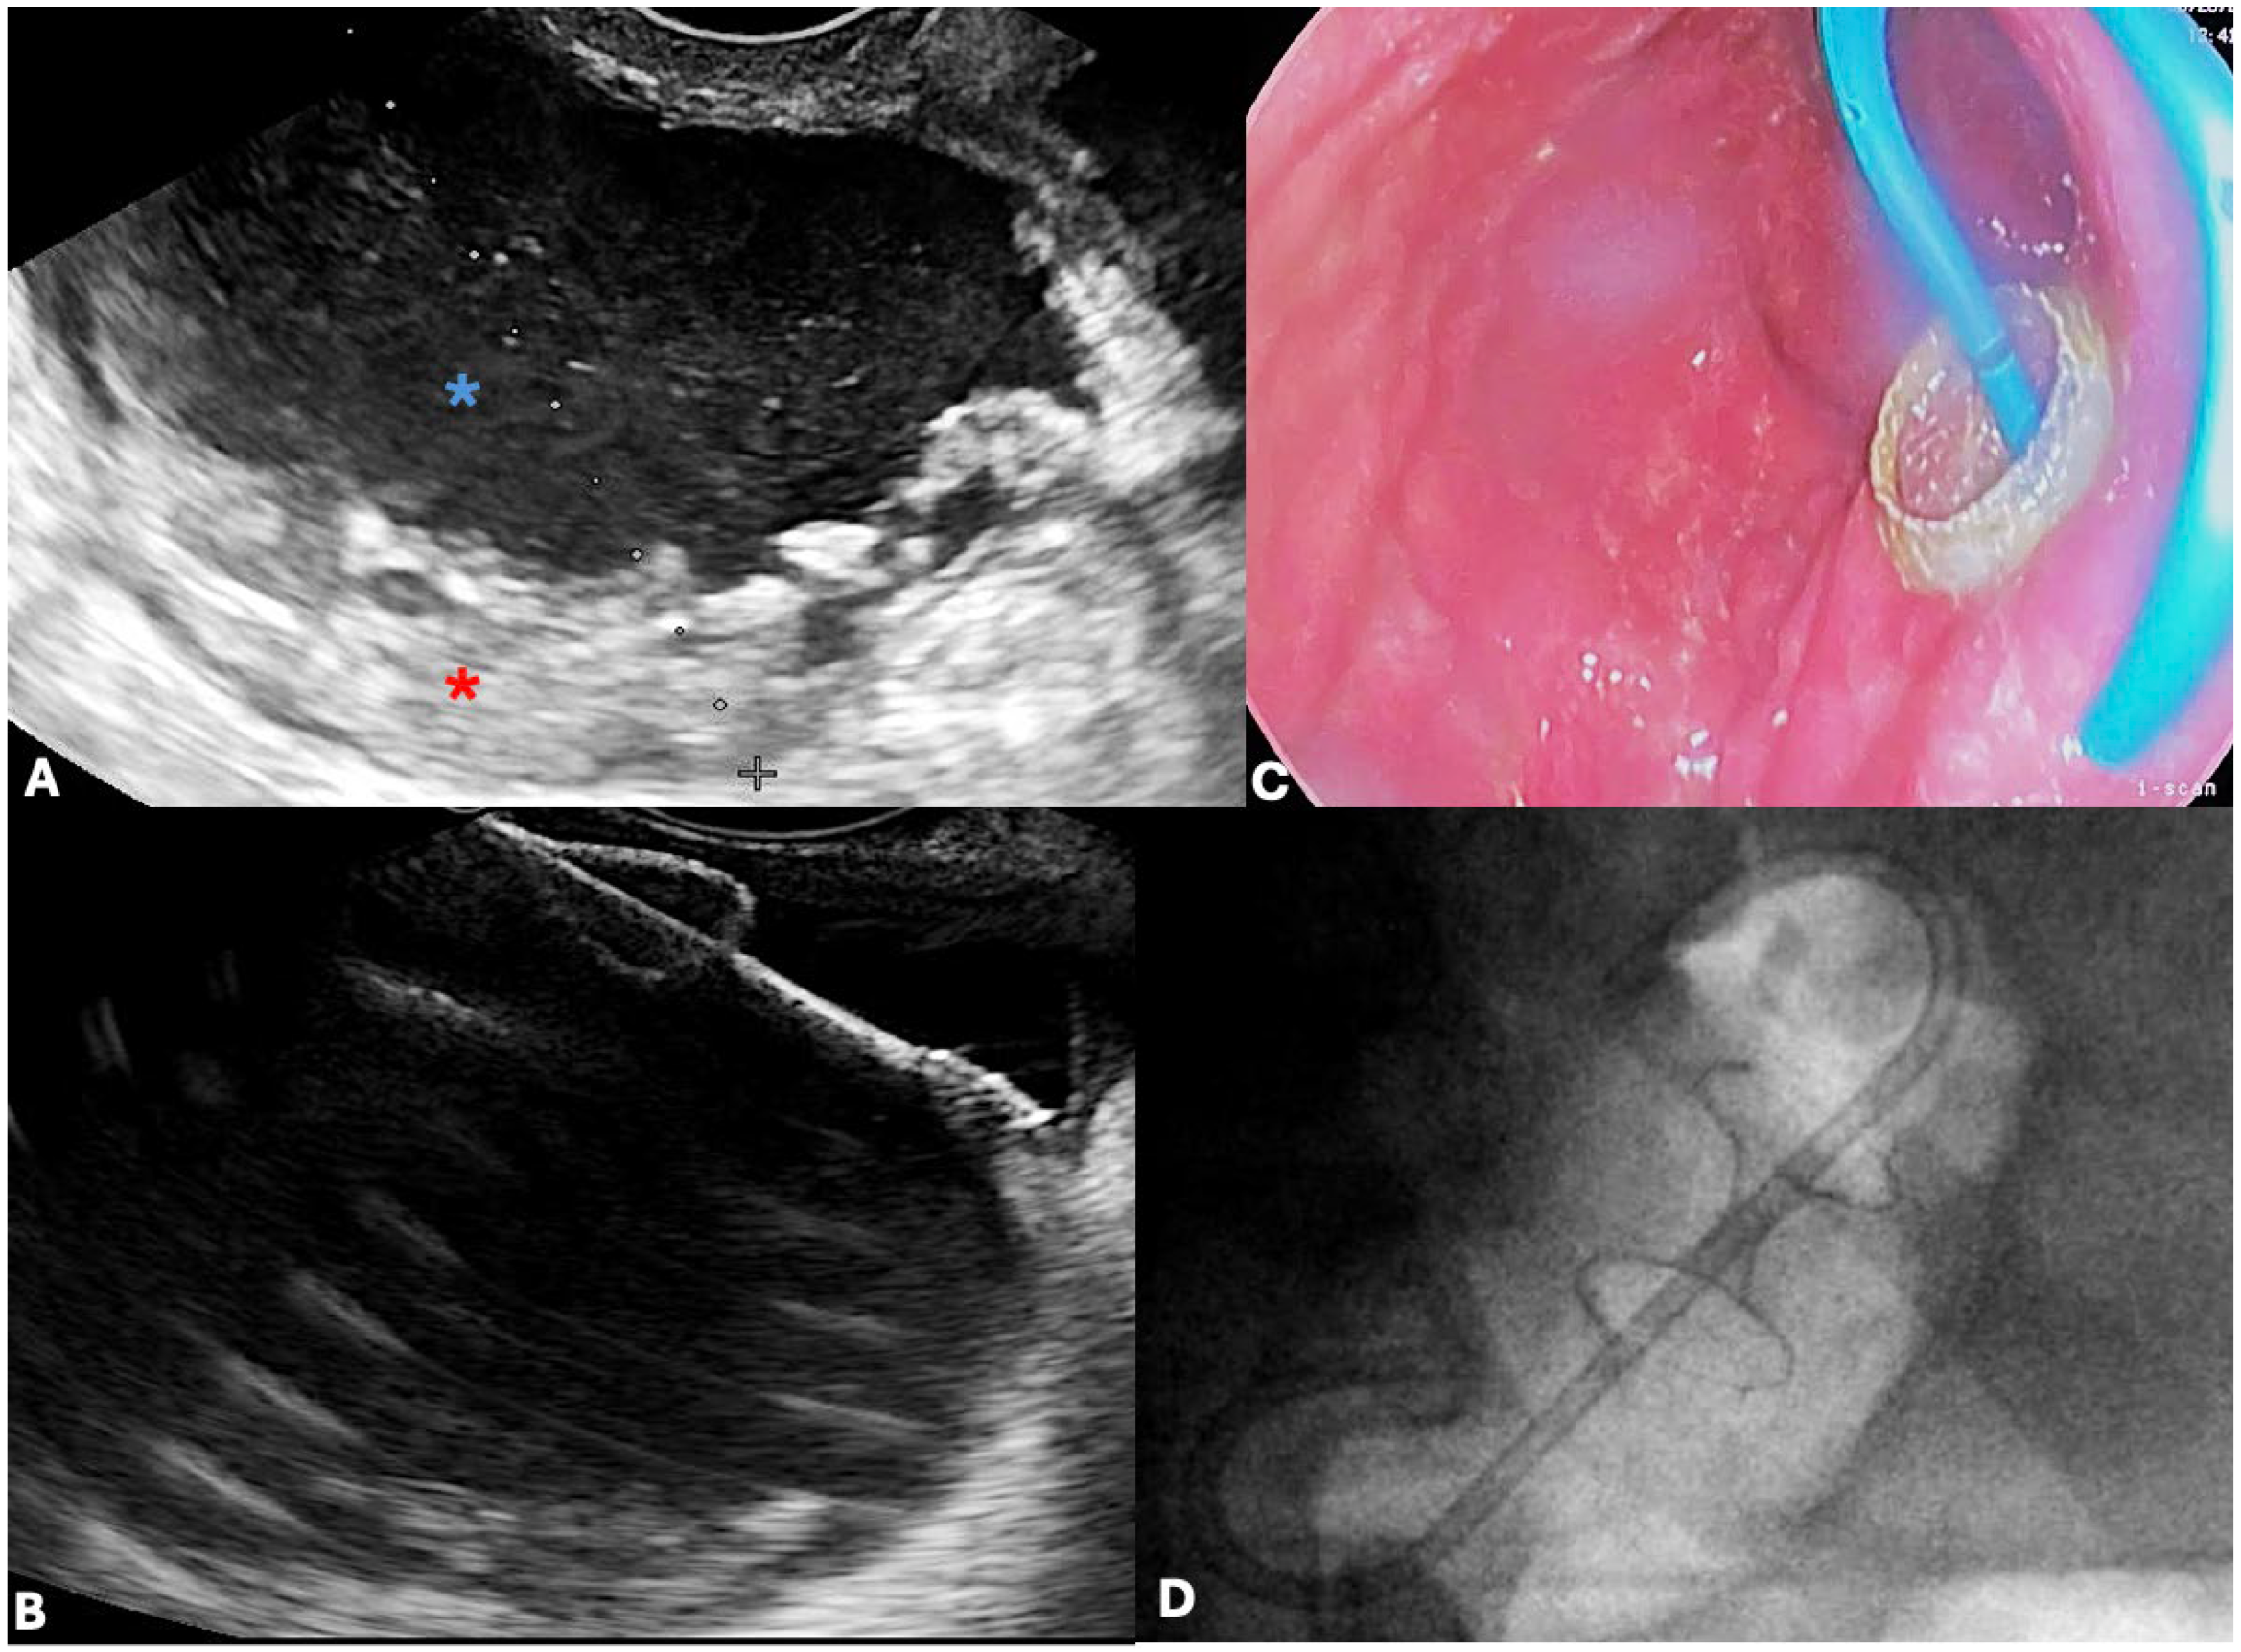

4.3. Role of Endoscopic Ultrasound (EUS)

- Vitali, F.; Zundler, S.; Jesper, D.; Strobel, D.; Wildner, D.; de Pretis, N.; Frulloni, L.; Crinó, S.F.; Neurath, M.F. Endoscopic Ultrasound in Pancreatology: Focus on Inflammatory Diseases and Interventions. Visc. Med. 2023, 39, 131–139. [Google Scholar] [CrossRef]

- Medarapalem, J.B.; Appasani, S.; Gulati, A.; Manrai, M.; Siddappa, P.K.K.; Khandelwal, N.; Sinha, S.K.; Gupta, V.; Yadav, T.D.; Kochhar, R. Mo1460 Characterization of Fluid Collections Using Quantification of Solid Debris in Acute Pancreatitis—A Comparative Study of EUS vs. CT for Prediction of Intervention. Gastrointest. Endosc. 2014, 79, AB445. [Google Scholar] [CrossRef]